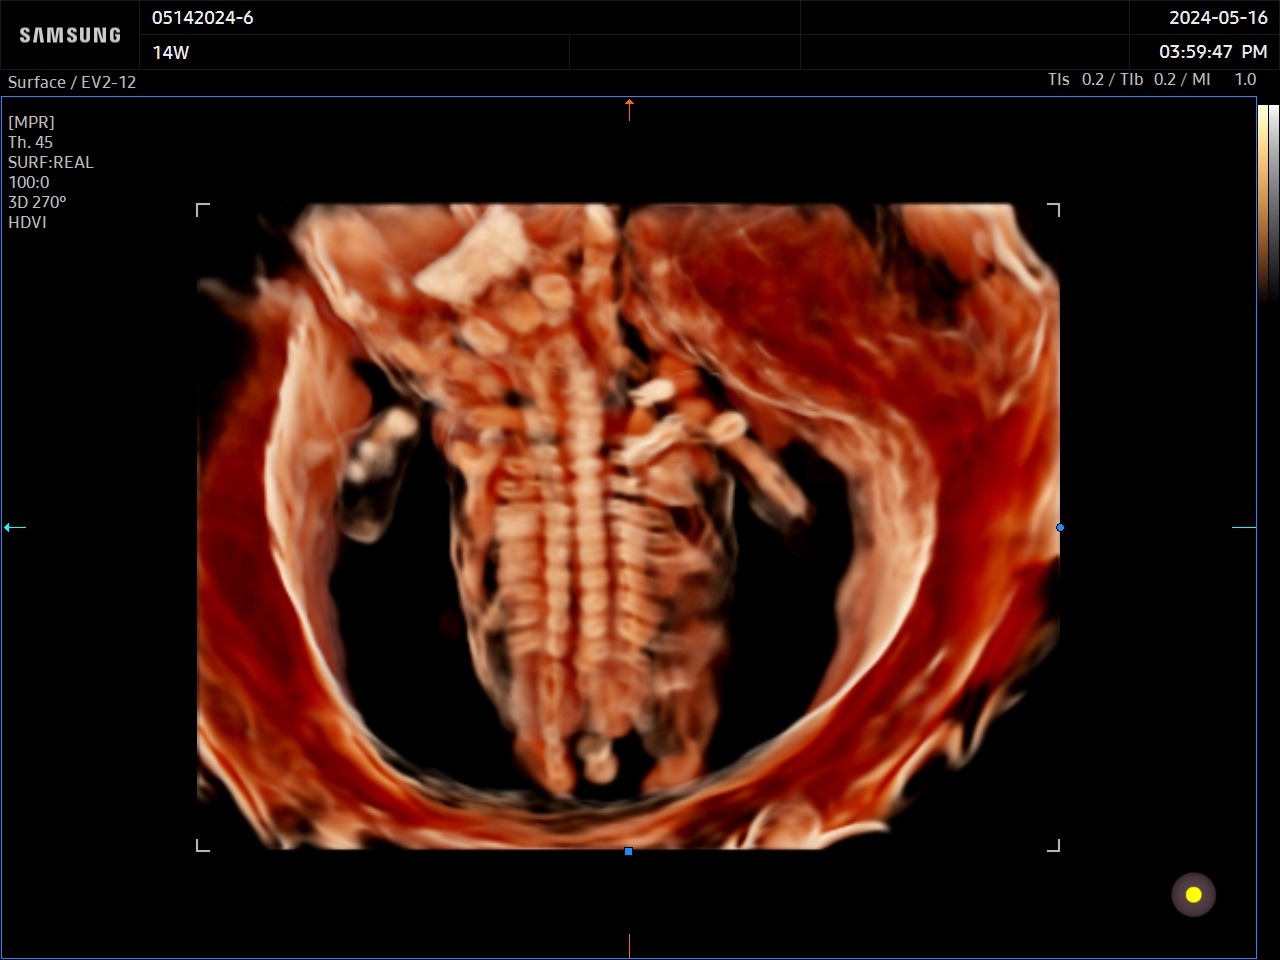

RealisticVue™ affiche une anatomie 3D haute résolution et une perception réaliste de la profondeur. Une source lumineuse est modélisée afin de permettre un effet d’ombre sur les structures et de surligner les zones d’intérêt.

CrystalVue™ est une technologie avancée qui permet de visualiser sur un rendu volumique, les structures tissulaires et les structures osseuses. Ce mode utilise la superposition des différentes échogénicités afin de permettre la visualisation de toutes les structures sur un même volume.